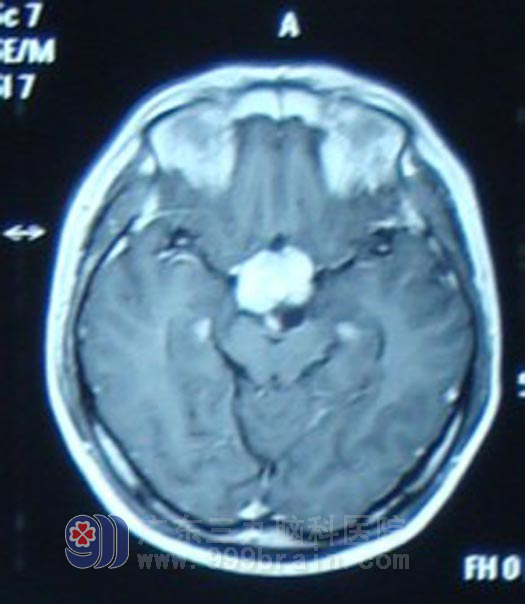

经人介绍,6月20日,小梁在家人陪同下来到广东三九脑科医院肿瘤综合治疗中心就诊。该中心蔡林波主任在了解小梁病史时发现,他除了视力下降(左眼视力0.1,右眼视力0.2)、视野发生改变外(双眼颞侧及上下侧视野缺损),近2个月以来还出现了多饮多尿现象,结合其影像学资料,蔡林波主任高度怀疑小梁患的是生殖细胞瘤,但确诊仍需要更多的临床资料。于是,抽取小梁的脑脊液进行化验检查,结果示HCG(人绒毛膜促性腺激素)值高出正常值10多倍,AFP(甲胎蛋白)也高于正常,这进一步证明小梁所患脑瘤为生殖细胞瘤的可能性极大。鉴于生殖细胞瘤首选放射治疗,蔡林波主任首先为小梁制定了定位适形诊断性放疗方案,放疗10Gy后,复查头颅MR显示肿物较前明显缩小,确诊为生殖细胞瘤。遂开始予全脑全脊髓放疗,完成54Gy后复查头颅MR显示肿瘤基本消失。患者症状明显改善,多饮多尿症状减轻,患者左眼视力恢复至0.4,右眼视力0.5。

放疗前